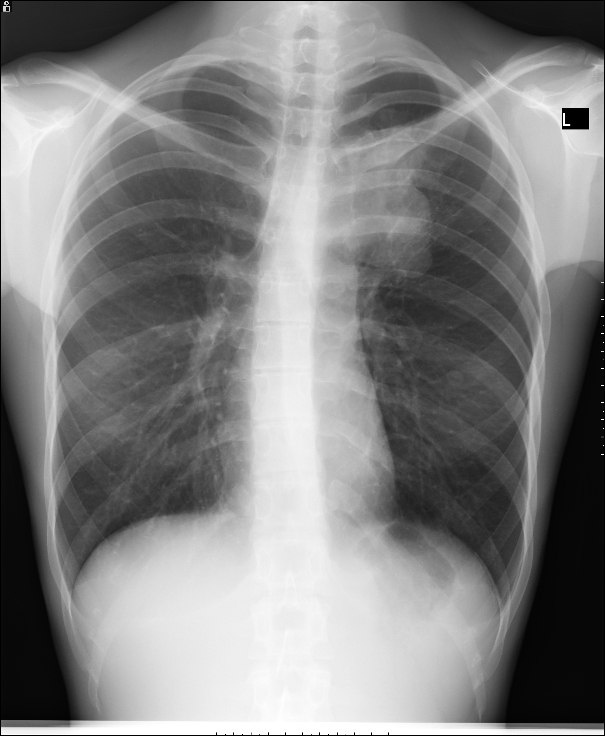

1. Рентгенография органов грудной клетки – первичный метод выявления кист.